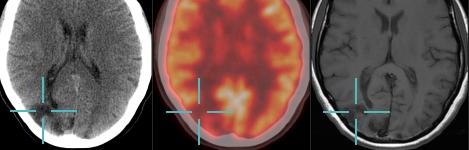

Image courtesy of Blackford Analysis

Blackford Analysis is a provider of software technology that accelerates the comparison of medical images by calculating and storing alignments with imaging studies. Blackford Analysis showcased its products at RSNA 2014.